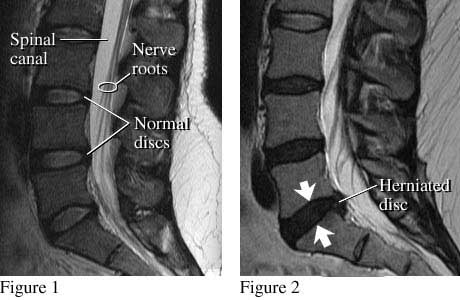

Images of normal discs and a herniated disc

A side view of the lumbar spine shows normal discs, spinal canal, and nerve roots (see figure 1). Nerve roots normally float in the fluid-filled canal. Figure 2 shows a small herniated disc pushing into the canal toward nerve roots.